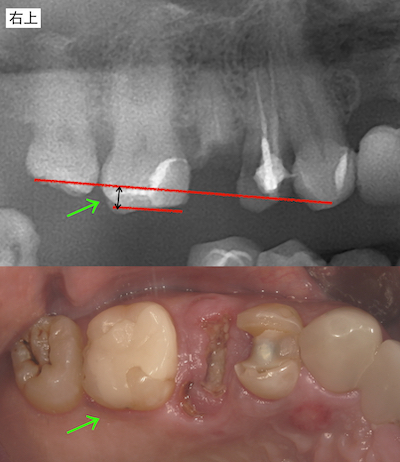

右上のアンカースクリューによる圧下の結果のレントゲンです。

アンカースクリューによる右上の圧下も終えて、上部構造を装着しました。